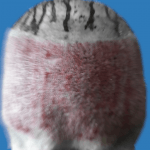

돌이킬 수 없는

결과

불법 진료소에 가면 무슨 일이 일어날 수 있나요?

| 끔찍한 감염 | 생명을 위협하는 합병증 | 끔찍한 결과 |